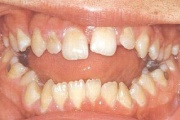

Puudub ülemine tsentraalne intsisiiv, kuid külgmised lõikehambad on juba lõikunud.

Turritavad ülemised lõikehambad.

Puudub ülemine tsentraalne intsisiiv